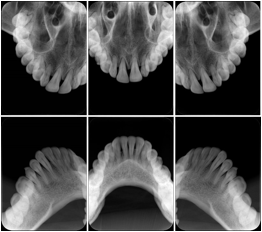

2. A patient requests cosmetic surgery to enhance their facial appearance. The case requires consultation between an orthodontist in New York and an oral surgeon in California. The cephalometric series of 2D projections constructed from a volumetric CT data set that is used for the discussion is arranged by a Structured Display for transfer between the two practitioners.

Cephalometric Series Structured Display

Figure OO-2. Cephalometric Series Structured Display

3. A dental provider wishes to capture a series of DICOM IO images for the patient’s dentition. The tooth morphology, teeth are divided into molars, premolars, canines and incisors, and a number of images for each jaw. The anatomic information was captured utilizing the triplet of schema. This standard code sequence is based on ISO 3950-2010, Dentistry - Designation system for teeth and areas of the oral cavity.

In most standard cases, images are oriented in structured layouts. These structured displays are useful to be shared between providers for reference purposes.

Table OO.1.1-1 shows structured display standard templates, where Viewset ID is based on the Japanese Society for Oral and Maxillofacial Radiology (JSOMR) classification provided by JIRA (Japan Medical Imaging and Radiological Systems Industries Association, www.jira-net.or.jp). Expected or typical teeth to be imaged location, region and designation codes are based on ISO 3950-2010, Dentistry - Designation system for teeth and areas of the oral cavity. For all the hanging protocols listed in OO.1.1-1, the value to use for Hanging Protocol Creator (0072,0008) is "JSOMR" and the value to use for Hanging Protocol Name (0072,0002) does not include "JSOMR" (e.g., "DL-S001A", not "JSOMR DL-S001A").